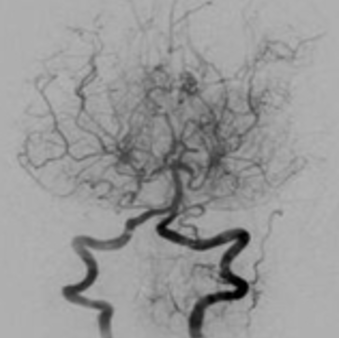

모야모야병은 특별한 이유 없이 두개 내 내경동맥의 끝부분, 즉, 전대뇌동맥과 중대뇌동맥 시작 부분에 협착이나 폐색이 보이고, 그 부근에 모야모야 혈관이라는 이상 혈관이 관찰되는 질병입니다.

1969년 스즈끼(Suzuki)에 의해 뇌혈관 동맥 조영상에 따라 일본말로 “담배연기가 모락모락 올라가는 모양”의 뜻을 지닌 모야모야병으로 명명되었습니다.